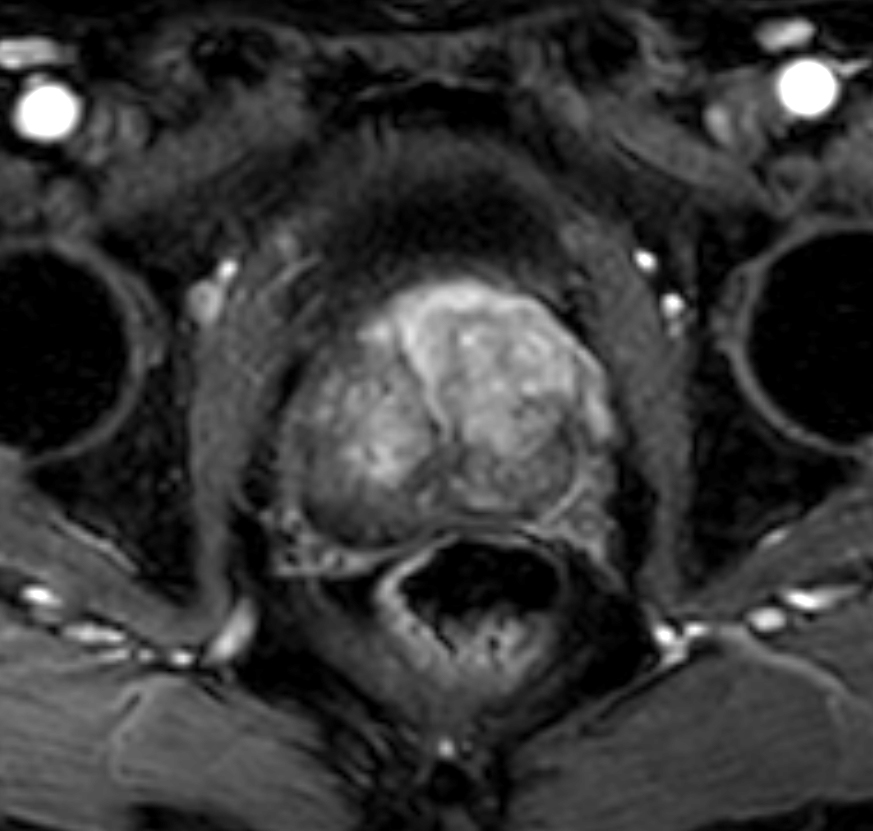

Axial T2w TSE FatSat

Axial T2w TSE - MultiVane XD